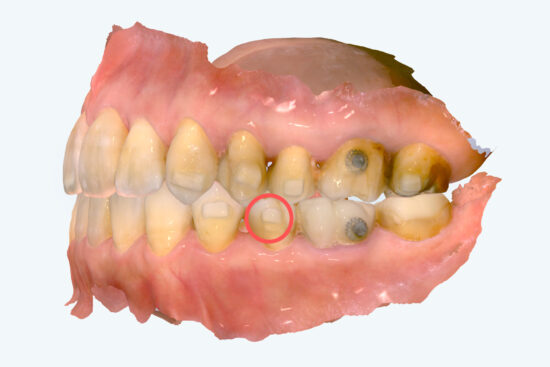

歯周病とは?

簡単に言うと、歯周病は歯槽骨や歯茎が歯を支えきれなくなる病気です。

歯槽骨が薄くなると、歯を支える力が弱まり、最終的に歯を失う原因にもなりかねません。